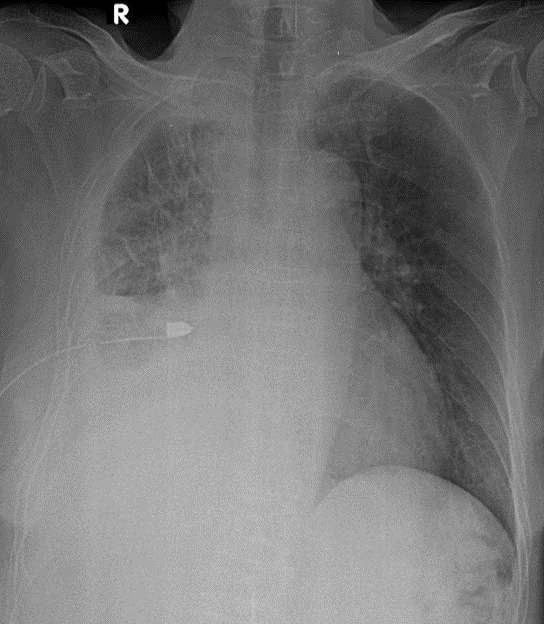

1-Thâm nhiểm phế nang lan tỏa phổi (P)=> VIÊM PHỔI 2-Tràn dịch màng phổi (P) lượng trung bình 3-Cung động mạch chủ dãn 4-Đang dẩn lưu màng phổi (P)